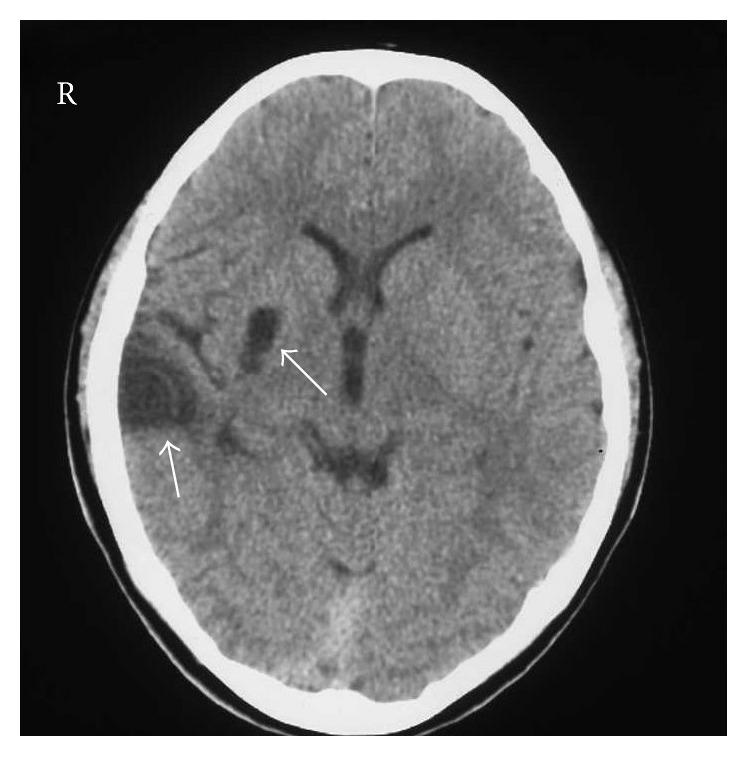

The grasp reflex is a distressing symptom but the need to treat or suppress it has rarely been discussed in the literature. We report the case of a 17-year-old man who had suffered cerebral infarction of the right putamen and temporal lobe 10 years previously. Forced grasping of the hemiparetic left upper limb was improved after a unique combined treatment. Botulinum toxin type A (BTX-A) was first injected into the left biceps, wrist flexor muscles, and finger flexor muscles. Forced grasping was reduced along with spasticity of the upper limb. In addition, repetitive facilitative exercise and object-related training were performed under low-amplitude continuous neuromuscular electrical stimulation. Since this 2-week treatment improved upper limb function, we compared brain activities, as measured by near-infrared spectroscopy during finger pinching, before and after the combined treatment. Brain activities in the ipsilesional sensorimotor cortex (SMC) and medial frontal cortex (MFC) during pinching under electrical stimulation after treatment were greater than those before. The results suggest that training under electrical stimulation after BTX-A treatment may modulate the activities of the ipsilesional SMC and MFC and lead to functional improvement of the affected upper limb with forced grasping.

抓握反射是一种令人苦恼的症状,但在文献中很少讨论治疗或抑制它的必要性。我们报告一例17岁男性病例,该患者10年前曾患右侧壳核和颞叶脑梗死。经过独特的联合治疗后,偏瘫的左上肢的强制抓握得到改善。首先将A型肉毒杆菌毒素(BTX-A)注射到左肱二头肌、腕屈肌和指屈肌。随着上肢痉挛的减轻,强制抓握也减少了。此外,在低强度连续神经肌肉电刺激下进行重复性促进运动和与物体相关的训练。由于这两周的治疗改善了上肢功能,我们比较了联合治疗前后通过近红外光谱测量的手指捏合时的脑活动。治疗后电刺激下捏合期间,患侧感觉运动皮层(SMC)和内侧额叶皮层(MFC)的脑活动大于治疗前。结果表明,BTX-A治疗后在电刺激下进行训练可能会调节患侧SMC和MFC的活动,并导致患侧上肢强制抓握功能的改善。